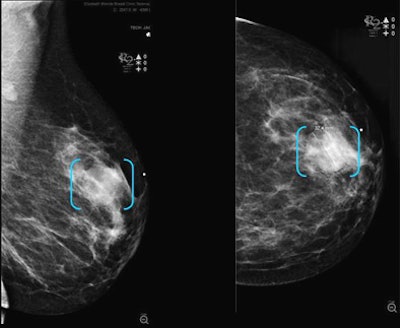

![]() |

| Sensitivity results show variable CAD sensitivity based on lesion type and mammography projection. CAD found the greatest number of masses on craniocaudal views. |

What did CAD find where? Three of the masses were detected on MLO, six at CC, and four on both projections. Among the calcifications, 60 were detected on both MLO and CC, two on CC alone, and one on MLO alone.

CAD detected the asymmetric densities in both MLO and CC views. For the masses, three were detected on MLO, six at CC, and four on both views. Among the calcifications, 60 were detected on both MLO and CC, two on CC alone, and one on MLO alone. CAD detected all masses with calcification and architectural distortion on both views.

"When you take the lesions marked for every view over the number of cases we know are visible on both CC and MLO views, the image sensitivity was 69% (31/45) for MLO and 78% (35/45) for the CC view," she said.